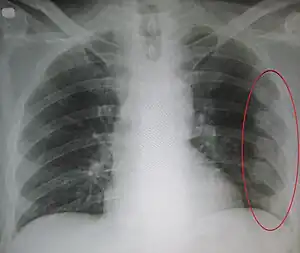

Respiratory causes

pneumothorax